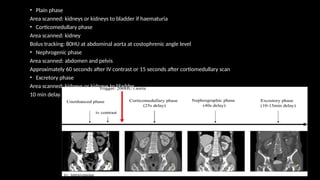

• Plain phase

Area scanned: kidneys or kidneys to bladder if haematuria

• Corticomedullary phase

Area scanned: kidney

Bolus tracking: 80HU at abdominal aorta at costophrenic angle level

• Nephrogenic phase

Area scanned: abdomen and pelvis

Approximately 60 seconds after IV contrast or 15 seconds after cortiomedullary scan

• Excretory phase

Area scanned: kidneys or kidneys to bladder

10 min delay